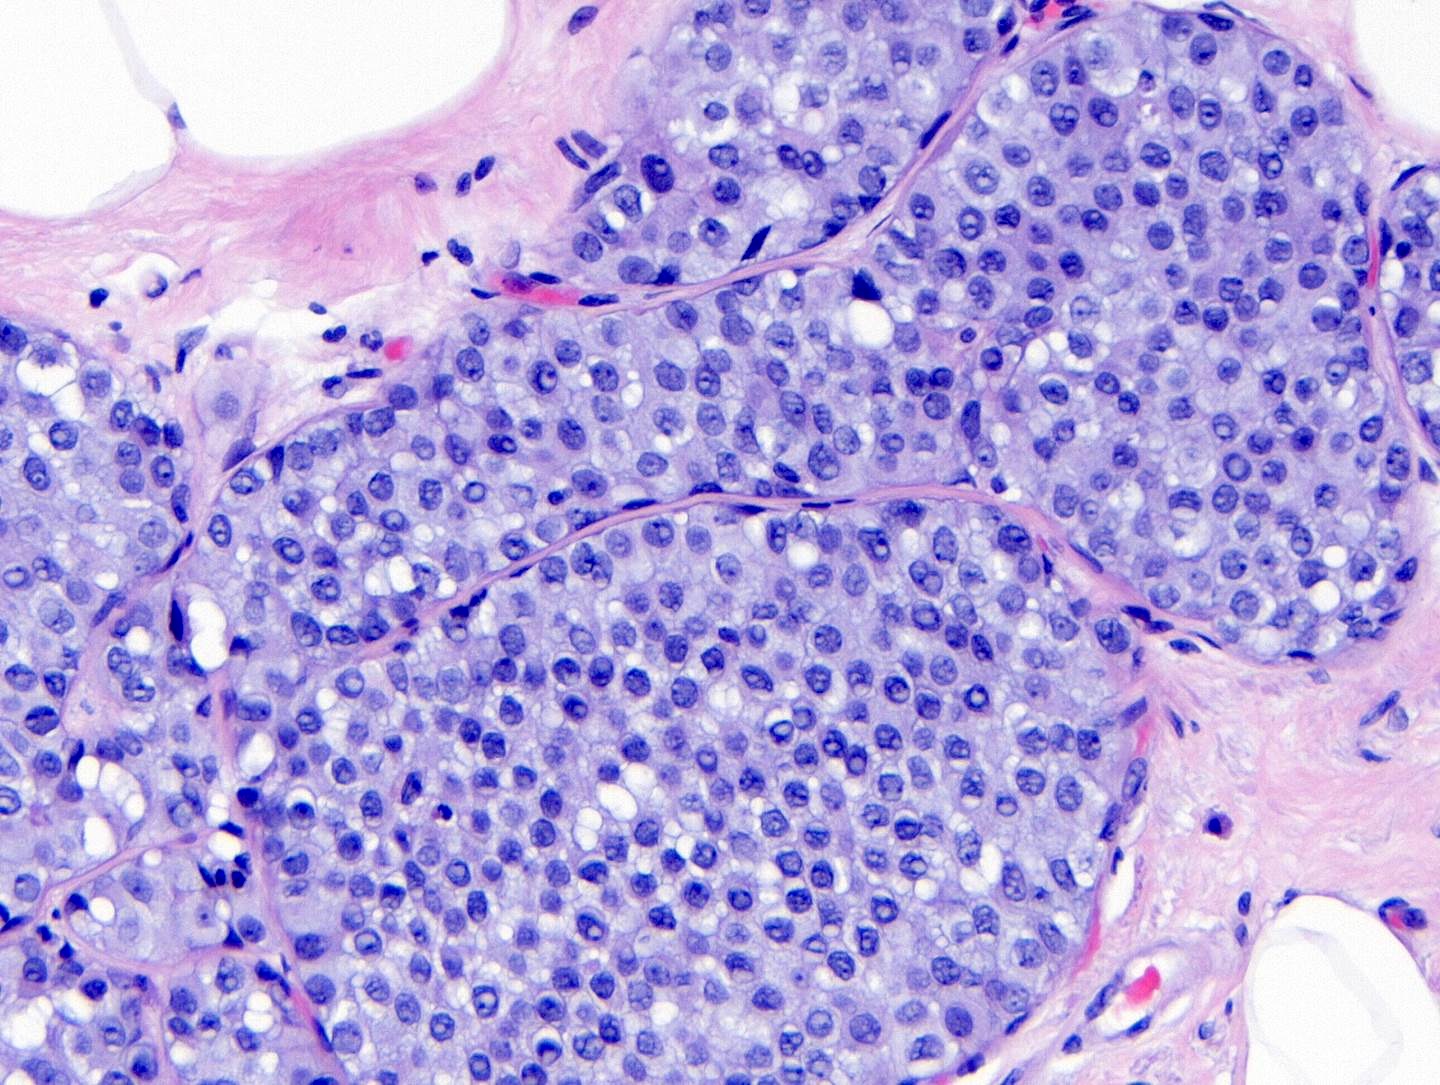

Microscopic (histologic) images

Contributed by Anna Biernacka, M.D., Ph.D.

- Classic LCIS cells are monomorphic, evenly spaced, loosely cohesive and do not show polarization or gland formation

- Type A: nuclei are small to slightly enlarged (1 - 1.5x size of lymphocyte) with uniform round nuclei and inconspicuous nucleoli

- Type B: nuclei larger (2x size of lymphocyte), more abundant cytoplasm and more prominent nucleoli

- Type A and B cells can coexist in the same lesion

- Cytoplasm of LCIS cells is typically pale to lightly eosinophilic with indistinct cell borders

- In almost all cases of LCIS, at least some cells contain intracytoplasmic vacuoles or lumina, which may contain an eosinophilic globule; this feature is not specific to LCIS

- Vacuoles may be subtle such that special histochemical stains for mucin are required in order to demonstrate; alternatively, they may be large enough to push the nucleus against the cell membrane and produce signet ring cell forms

- Outer layer of myoepithelial cells is retained in the acini and ducts involved but it may be attenuated

- In some cases, scattered myoepithelial cells can be admixed with the neoplastic epithelial cells within the involved spaces

- Classic LCIS does not show significant nuclear pleomorphism or mitosis

- Classic LCIS may rarely display single cell apoptosis or minute foci of necrosis but typically does not show comedo type necrosis